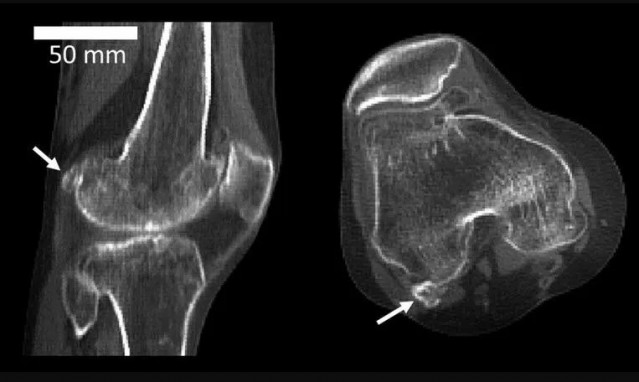

Fabela lateral en la parte posterior de una rodilla humana

La fabela lateral es un hueso sesamoideo detrás de la rodilla que es dos veces más común en personas con osteoartritis de rodilla. Los sesamoideos, como la rótula, son huesos pequeños incrustados en tendones o ligamentos que a veces están presentes en los esqueletos de los mamíferos, lo que significa que pueden estar ausentes en algunos mamíferos, pero presentes en otros de la misma especie.